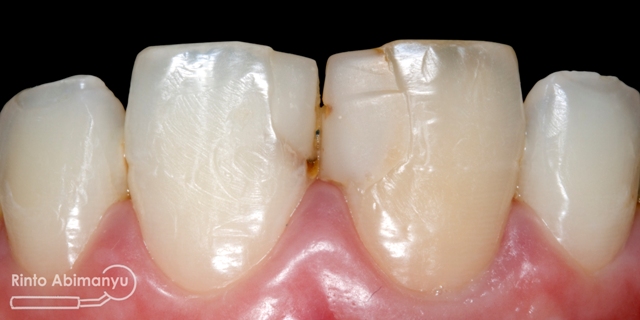

Ini kondisi gigi pada saat datang…

Kondisi awal gigi 11

Terlihat kondisi gigi 11 dan 21 yang ada tambalannya di mesial, ada karies sekunder dan bentuk tambalan tidak mengikuti anatomi gigi 11 dan 21 seharusnya…